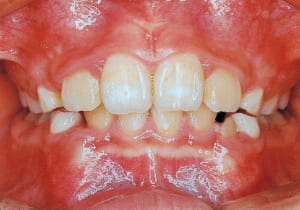

2 After Phase 2 Treatment 6-6-’94

11 After Phase 1 Treatment 5-24-’89

12 After Phase 1 Treatment 5-24-’89

The first phase of treatment involved extracting the left and right maxillary deciduous canines. The space created was used to forcibly retract the four anterior teeth, thereby aiming to improve lip closure function (6–9, 11). Morphological changes suggest that lip function differed before and after treatment (6, 9). Subsequently, the first premolars erupted, but extraction is planned to secure space for canine eruption (10). A Class II molar relationship remains, but the significant overjet has improved (11).